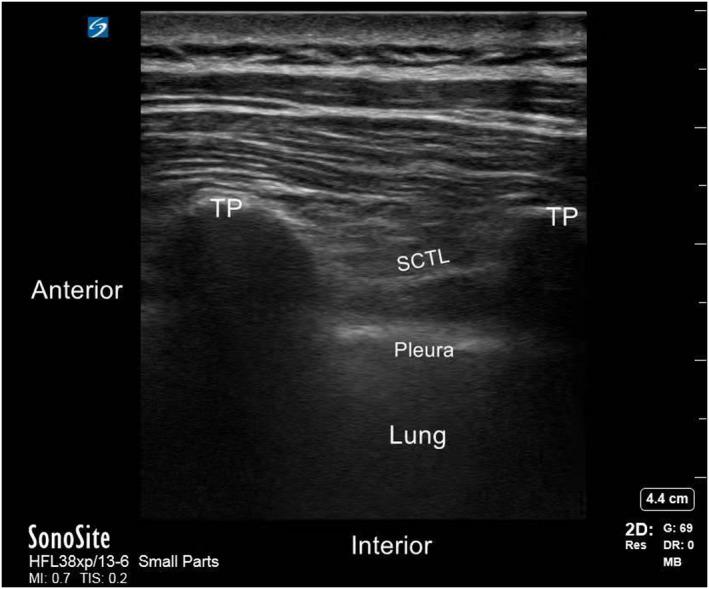

Efforts to prolong thoracic paravertebral block (TPVB) analgesia include local anesthetic adjuvants, such as dexamethasone (Dex). Previous studies showed that both perineural (PN) and intravenous (i.v.) routes could prolong analgesia. As PN Dex is an off-label use, anesthesiologists should be fully informed of the clinical differences, if any, on block duration. This study was designed to evaluate the two administration routes of Dex for duration of analgesia in TPVB. Ninety-five patients scheduled for Ivor-Lewis esophagectomy were randomized to receive TPVB (0.5% ropivacaine 15 ml), PN or i.v. Dex 8 mg. The primary end point was the duration of analgesia. The secondary end points included pain scores, analgesic consumption, adverse effects rate, and incidence of chronic pain at 3 months postoperatively. The PN-Dex group showed better analgesic effects than the i.v.-Dex group (p < 0.05). Similarly, the visual analogue scale scores in patients at 2, 4, 8, and 12 h postoperatively were lower in the PN-Dex group than the i.v.-Dex group (p < 0.05). The analgesic consumption in both the PN-Dex and i.v.-Dex groups was significantly lower than that in the control group (p < 0.05). Regarding the incidence of chronic pain, regardless of route, Dex decreased the incidence of chronic postsurgical pain and neuropathic pain at 3 months after surgery (p < 0.05), but there were no clinical differences between the i.v.-Dex and PN-Dex groups. Perineural dexamethasone improved the magnitude and duration of analgesia compared to that of the i.v.-Dex group in TPVB in Ivor-Lewis esophagectomy. However, there were no clinically significant differences between the two groups in the incidence of chronic pain.

为延长胸段椎旁阻滞(TPVB)镇痛时间,可加入局部麻醉药佐剂,如地塞米松(Dex)。既往研究表明,经外周神经(PN)和静脉(iv.)途径均可延长镇痛时间。由于 PN 给予 Dex 为超说明书用药,麻醉医生应充分了解两种途径在阻滞持续时间上的临床差异。本研究旨在评估 PN 和 iv. 给予 Dex 对 TPVB 中镇痛持续时间的影响。95 例行 Ivor-Lewis 食管癌切除术的患者随机分为三组,分别接受 TPVB(0.5%罗哌卡因 15ml)、PN 或 iv. 给予 Dex 8mg。主要终点为镇痛持续时间。次要终点包括疼痛评分、镇痛药用量、不良反应发生率以及术后 3 个月慢性疼痛发生率。PN-Dex 组镇痛效果优于 iv.-Dex 组(p<0.05)。同样,PN-Dex 组患者术后 2、4、8 和 12h 的视觉模拟评分(VAS)均低于 iv.-Dex 组(p<0.05)。PN-Dex 和 iv.-Dex 组的镇痛药用量均显著低于对照组(p<0.05)。无论给药途径如何,Dex 均降低了术后 3 个月慢性术后痛和神经病理性疼痛的发生率(p<0.05),但 iv.-Dex 组与 PN-Dex 组之间无临床差异。与 iv.-Dex 组相比,PN 给予 Dex 可提高食管癌 Ivor-Lewis 手术中 TPVB 的镇痛效果和持续时间。然而,两组慢性疼痛的发生率无显著差异。